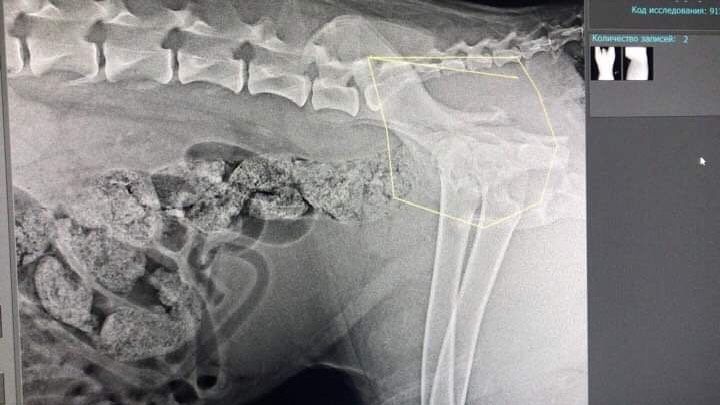

Двойной перелом таза без смещения. Чипа нет. Клеймо не рассмотреть -очень волосатое брюхо.

"надо показать снимки собаки специалистам,перелом со смещение,может надо оперировать и ставить пластину"

Фауста прооперировали